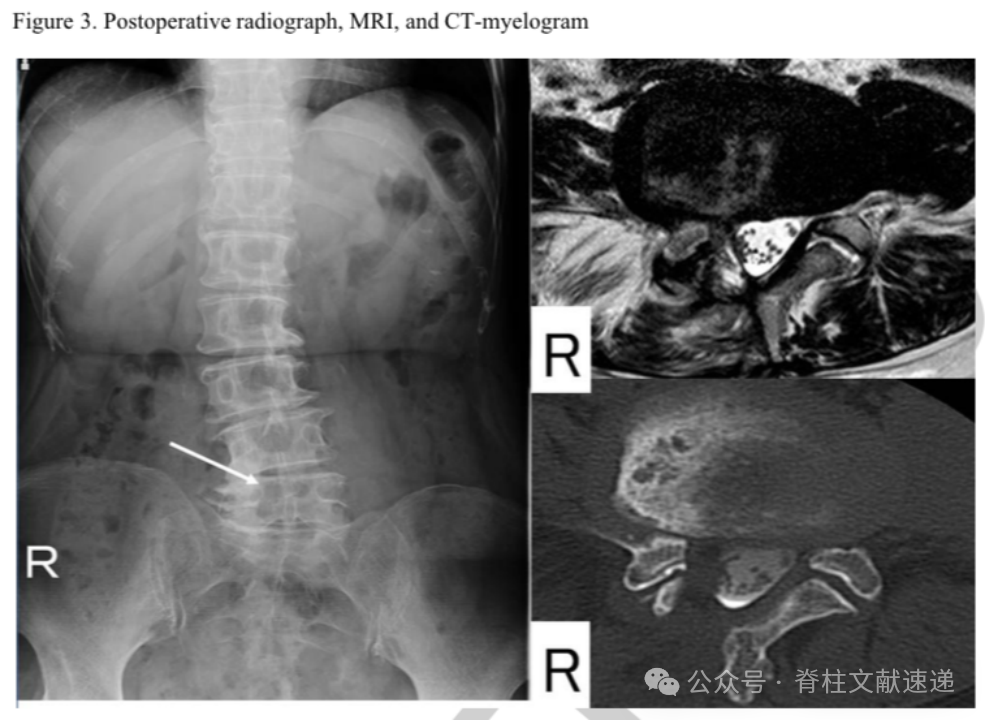

文中病例:69岁女性,右下肢放射性疼痛。存在脊柱侧弯,髓核摘除术后2月进行了融合手术。